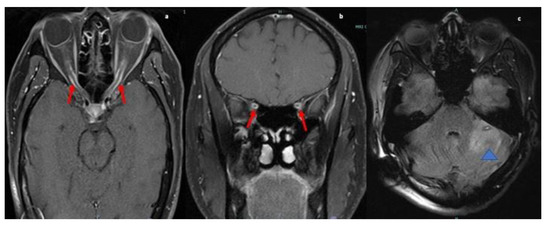

Figure 5.

MRI orbit axial T1-weighted fat-suppressed post contrast image (a) and coronal (b) images reveal enhancement of bilateral optic nerve sheaths (red arrow). MRI Brain axial fluid-attenuated inversion recovery (FLAIR) (c) image reveals ill-defined patchy parenchymal hyperintensity in the left cerebellar hemisphere extending to the cerebellar peduncle (blue arrowhead).

MRI brain and orbits revealed an enhancing left cerebellar nodule with surrounding abnormal hyperintense signal on FLAIR extending to the cerebellar peduncle. Mass-like enhancement of the folia surrounding the nodule was also noted. MRI orbits showed bilateral smooth optic nerve sheath enhancement without abnormal signal within the optic nerves. There were also imaging findings concerning for papilledema with flattening of the posterior globes (refer Figure 5) and T2 images (not shown) also demonstrated intraocular protrusion of the optic nerve heads. These findings were most consistent with inflammatory processes such as sarcoid or possible leptomeningeal metastatic disease.

A lumbar puncture was performed, and a VP shunt was placed. CSF analysis revealed CSF protein of >400 mg/dL, elevated opening pressure, CSF ACE mildly elevated at 3.7 U/L (normal up to 2.5), 12 WBC predominant lymphocytic 90%, and negative meningitis panel. Serum ACE was normal. CT chest/abdomen/pelvis were without evidence of malignancy or systemic sarcoid.

The patient received left optic nerve sheath fenestration in an effort to decrease the swelling of the optic nerve. Biopsy of the left optic nerve sheath demonstrated findings concerning for NS. The patient was started on one dose of cyclophosphamide with Mesna and discharged with oral tapering prednisone starting at 60 mg dose, with a follow-up scheduled in neurology and ophthalmology clinics. Following the treatment, the patient continued to have lack of light perception in left eye but the visual acuity improved within the right eye to 20/40. Recommendation was to follow-up with the neurology outpatient clinic (refer Table 1)

The presenting symptoms of case five were retro-orbital pain, blurring of vision progressively leading to complete diminution and fundoscopic examination revealing papilledema consistent with increased ICP. However, cerebellar and cervical leptomeningeal enhancement were also discovered on MRI, and the patient exhibited no symptoms from these lesions. Hence, it appears that in some cases of NS the imaging findings may not correlate entirely with the clinical presentation of the disease.